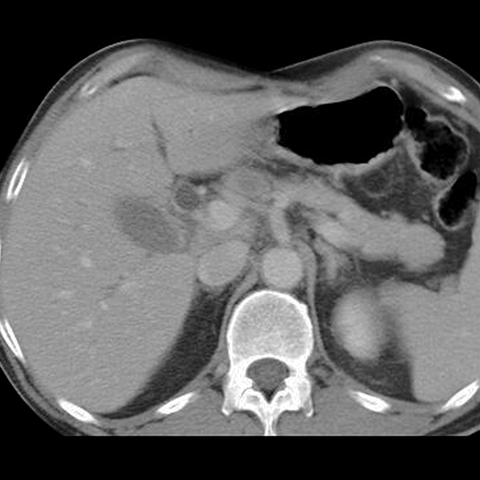

65-year-old male presents with painless jaundice. [2 of 5]